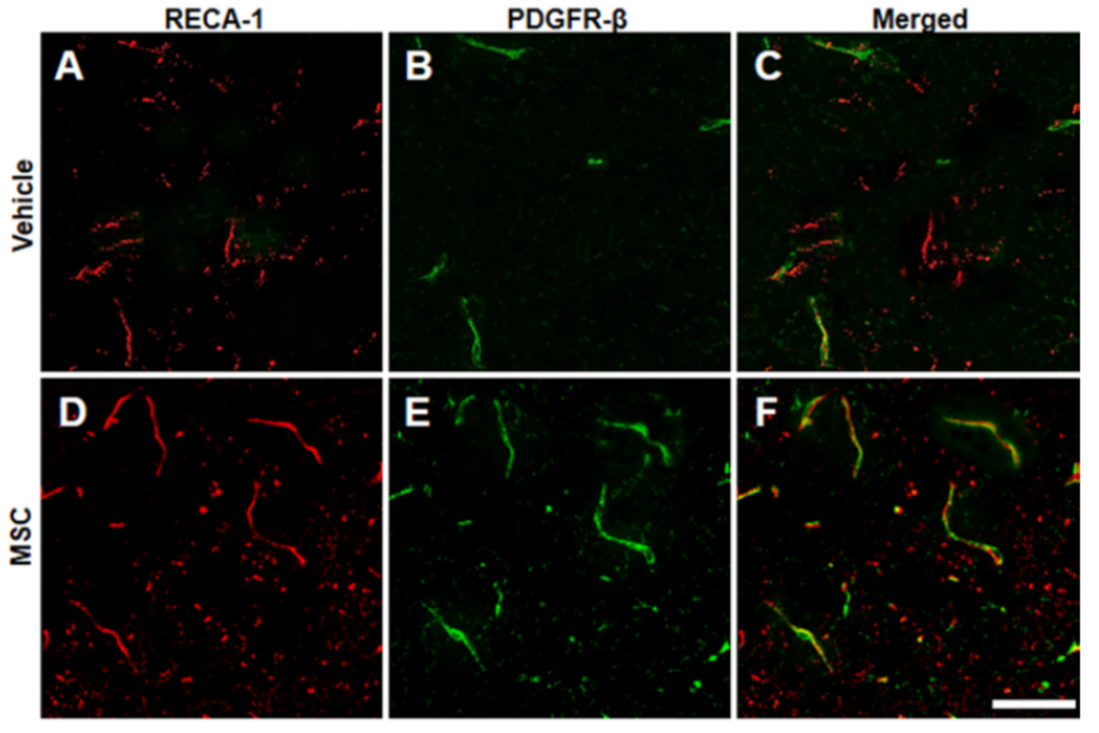

静脉输注骨髓间充质干细胞(MSCs)可改善大鼠脑梗死模型的行为学功能。虽然临床研究还在进行中,但大多数研究都集中在急性或亚急性期的卒中。本研究中在诱导大鼠大脑中动脉闭塞(MCAO)后8周,经静脉输注大鼠骨髓MSCs,以探讨延迟注射MSCs是否能改善大鼠卒中慢性期的功能预后。

作者在诱导大鼠大脑中动脉闭塞(MCAO)8周后,随机给大鼠静脉注射MSCs或溶剂。并检测大鼠的缺血体积和行为表现。本文通过静脉注射伊文思蓝后定量检测其渗漏到脑实质的量来评估血脑屏障的完整性。并利用免疫组化分析评估血脑屏障的稳定性。

结果显示,实验组大鼠的运动恢复情况优于对照组,且改善迅速(注射后1周可见明显改善)。在实验组大鼠中还观察到血脑屏障的渗漏减少,微循环改善和新生血管增加。这些结果表明,全身输注MSCs可通过稳定血脑屏障等,改善脑梗死慢性期的结构,从而促进神经功能的恢复。

图:免疫荧光结果显示MSC治疗组较对照组微循环明显改善。